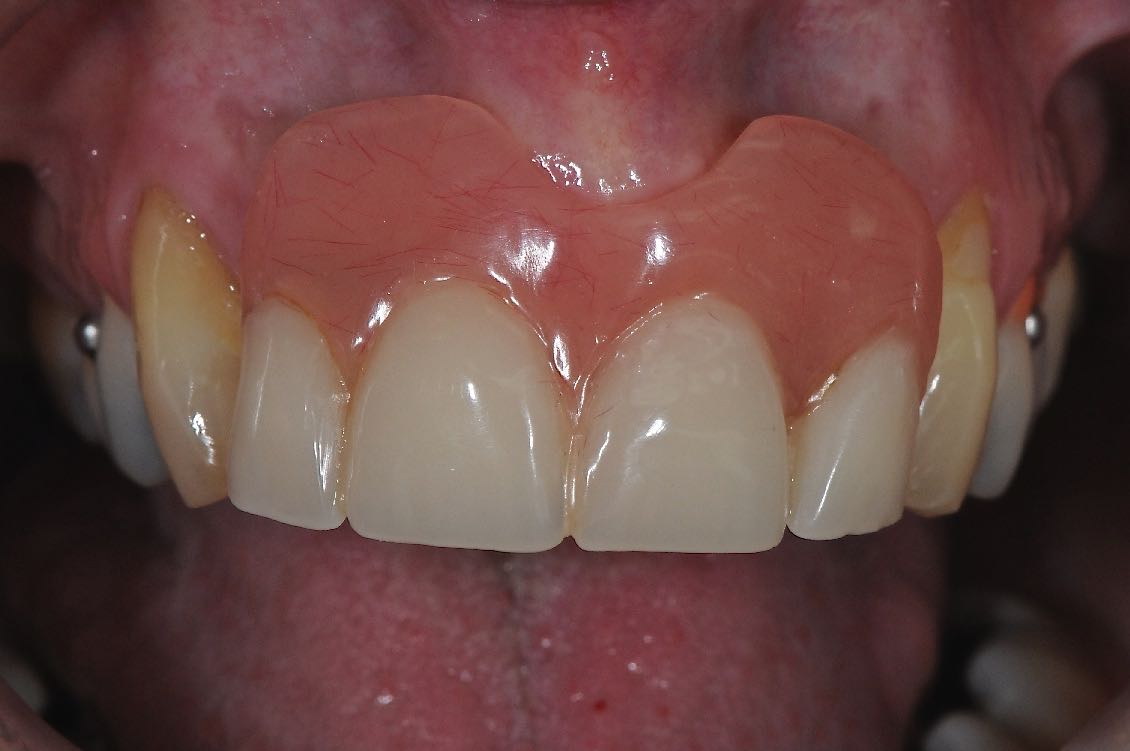

This lady presented seeking a permanent solution for her four missing incisor teeth. She lost the teeth many years ago in an accident, and had been fitted with a denture.

The denture was rather bulky with a lot of pink acrylic making it thick in the incisor region, under her lip. It was also a removable prosthesis which sometimes came loose. It always worried this lady that the denture may come loose at a socially awkward moment.

Two implants were placed and then a 4-tooth bridge was made and fitted to the implants. The bridge was secure, functional, and not as bulky as the denture.